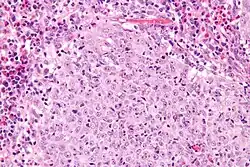

| Micrograph of a glassy cell carcinoma of the cervix. H&E stain. | |

Glassy cell carcinoma of the cervix, also glassy cell carcinoma, is a rare aggressive malignant tumour of the uterine cervix.[1] The tumour gets its name from its microscopic appearance; its cytoplasm has a glass-like appearance.

Under the microscope, glassy cell carcinoma tumours are composed of cells with a glass-like cytoplasm, typically associated with an inflammatory infiltrate abundant in eosinophils and very mitotically active. PAS staining highlights the plasma membrane.[2]

Low mag. High mag.

High mag.